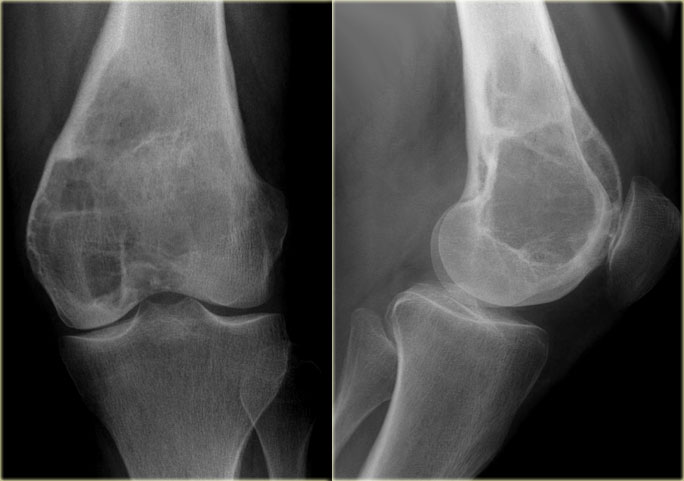

On the left more examples of GCT around the knee.

Notice that most of these lesions are well-defined and located in the epiphysis and extend into the metaphysis.

Some extend onto the articular surface (yellow arrow and small red arrows).

The lesion on the upper right has an ill-defined border with a broad zone of transition (blue arrow).